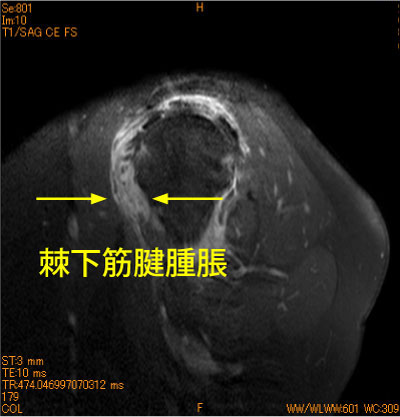

60代女性、長時間のマッサージの疼痛肩、造影後、脂肪抑制T1強調画像である。肩甲下筋の著明な腫脹と造影を認めている。

腱挫傷であるが、契機と肩甲下筋腱の損傷が稀である。

同部の腫脹は烏口突起との擦れの悪循環をつくる。

![]() Olb. sag T1 造影後 脂肪抑制 |